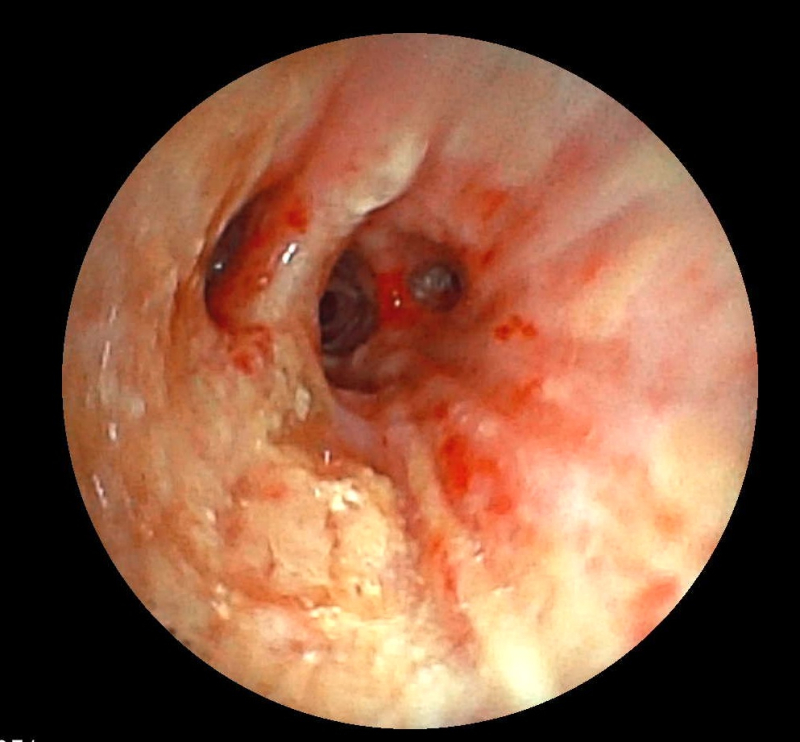

Hình ảnh dị vật góc cạnh khoảng 1cm là hạt kha tử hình bầu dục, bề mặt trơn nhẵn, hai đầu nhọn nằm chắn, gây bít tắc trong lòng phế quản gốc phải trên màn hình nội soi phế quản

Ekip của bác sĩ CKI Phạm Thị Út Trang – Phó Trưởng Khoa Nội hô hấp đã phối hợp với bác sĩ gây mê hồi sức đã nhanh chóng tiến hành nội soi phế quản ống mềm, phát hiện dị vật góc cạnh khoảng 1cm là hạt kha tử hình bầu dục, bề mặt trơn nhẵn, hai đầu nhọn nằm chắn, gây bít tắc trong lòng phế quản gốc phải, ngay sát vị trí chia nhánh phế quản phân thùy- khu vực giải phẫu hẹp, góc rẽ nhánh phức tạp khiến việc gắp dị vật gặp khó khăn. Ekip nội soi can thiệp đã khéo léo tiếp cận và thành công gắp dị vật ra khỏi lòng phế quản. Sau can thiệp, sức khỏe của bệnh nhân ổn định, thở dễ dàng, không còn cảm giác tức ngực, được xuất viện sau 24h theo dõi.